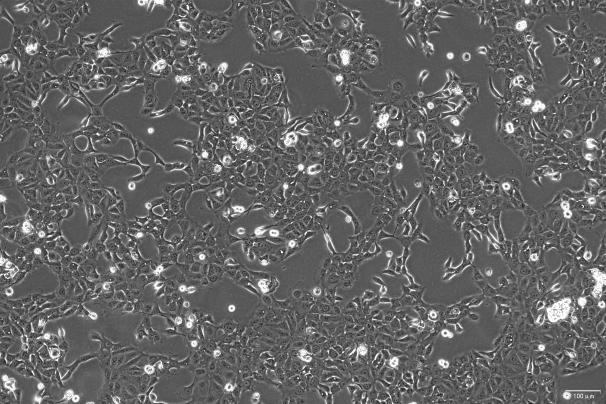

OriCell®LNCaP Clone FGC 人前列腺癌细胞系

人前列腺癌细胞系(LNCaP clone FGC)是从一位 50 岁白人男性(血型 B+)的左锁骨淋巴结针刺活检中分离,该患者经确诊为前列腺癌转移,该株细胞对 5-α-二氢睾酮(生长调节子和酸性磷酸脂酶产物)有响应,表达人前列腺酸性磷酸酶和前列腺特异性抗原。

贴壁生长;上皮细胞样 |